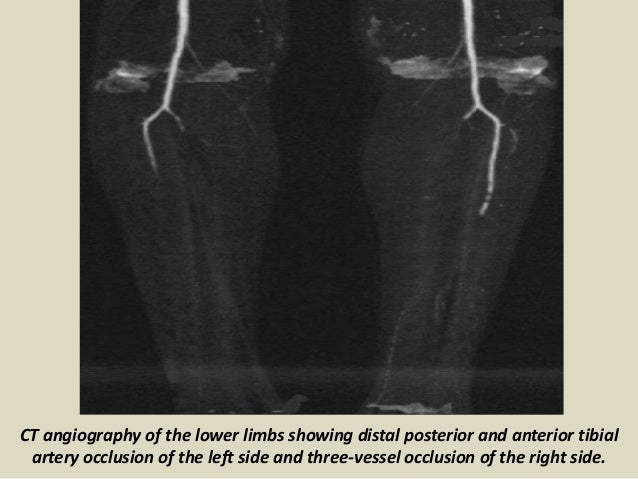

Ct Angiography Of The Lower Limbs Showing Distal Posterior And Anterior Download Scientific Diagram